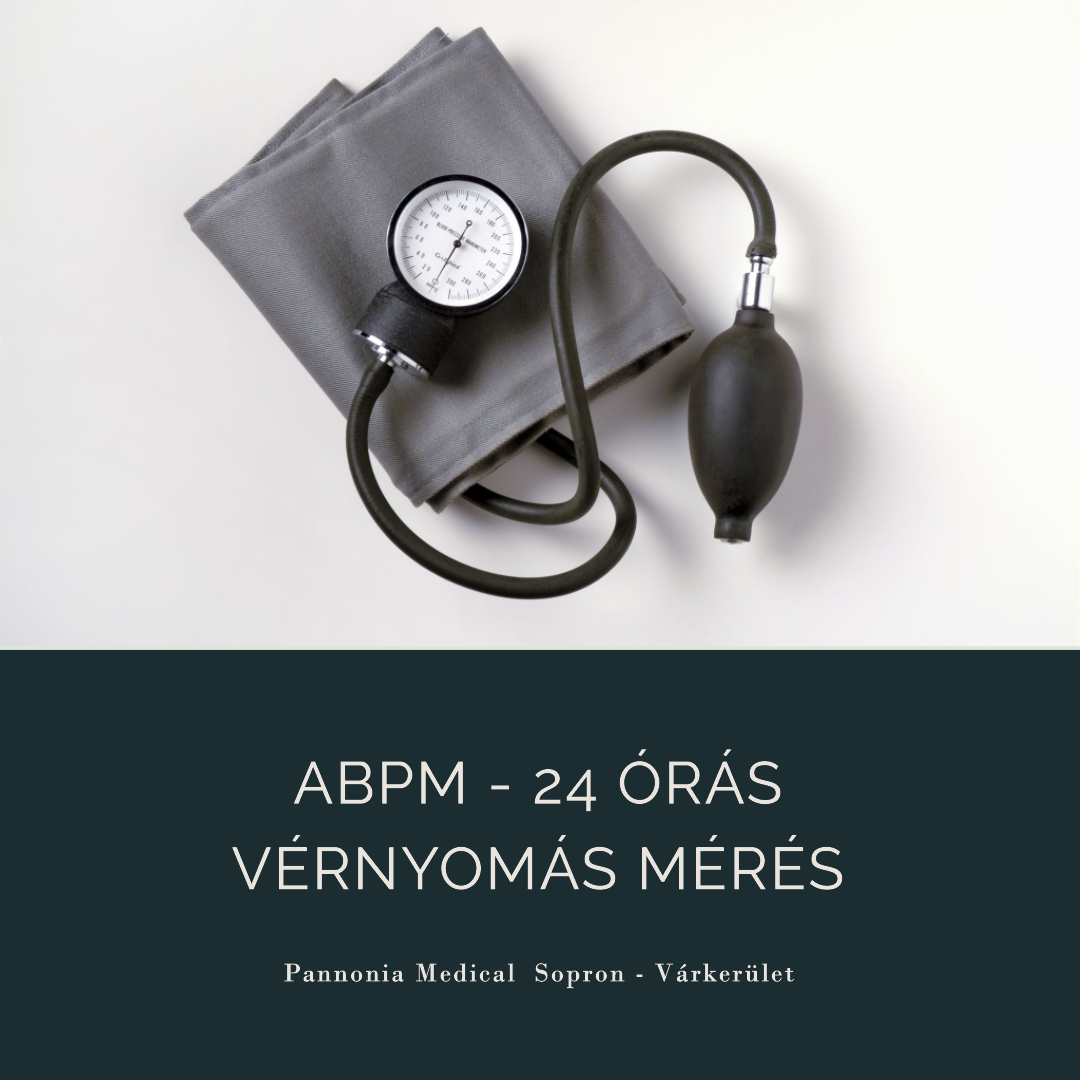

24 órás ABPM holter vizsgálat

ABPM Holter vizsgálat Sopronban

Az ABPM szűrés során a páciens 24 órán át visel egy kisméretű, hordozható eszközt, amely rendszeres időközönként méri a vérnyomást. A vizsgálat segítségével a kezelőorvosnak teljes képe lesz a páciens vérnyomásának napi változásairól, beleértve a napi tevékenységek és az alvás során történő változásokat is. Ezáltal a hagyományos, rendelőben végzett mérésekhez képest sokkal pontosabb képet kap a páciens vérnyomásáról, mivel a mérési eredmények nem torzulnak az úgynevezett „fehérköpeny-hatás” miatt, ami sokaknál a rendelőben történő vérnyomásmérés során tapasztalható.

ABPM Holter vizsgálatokról bővebben